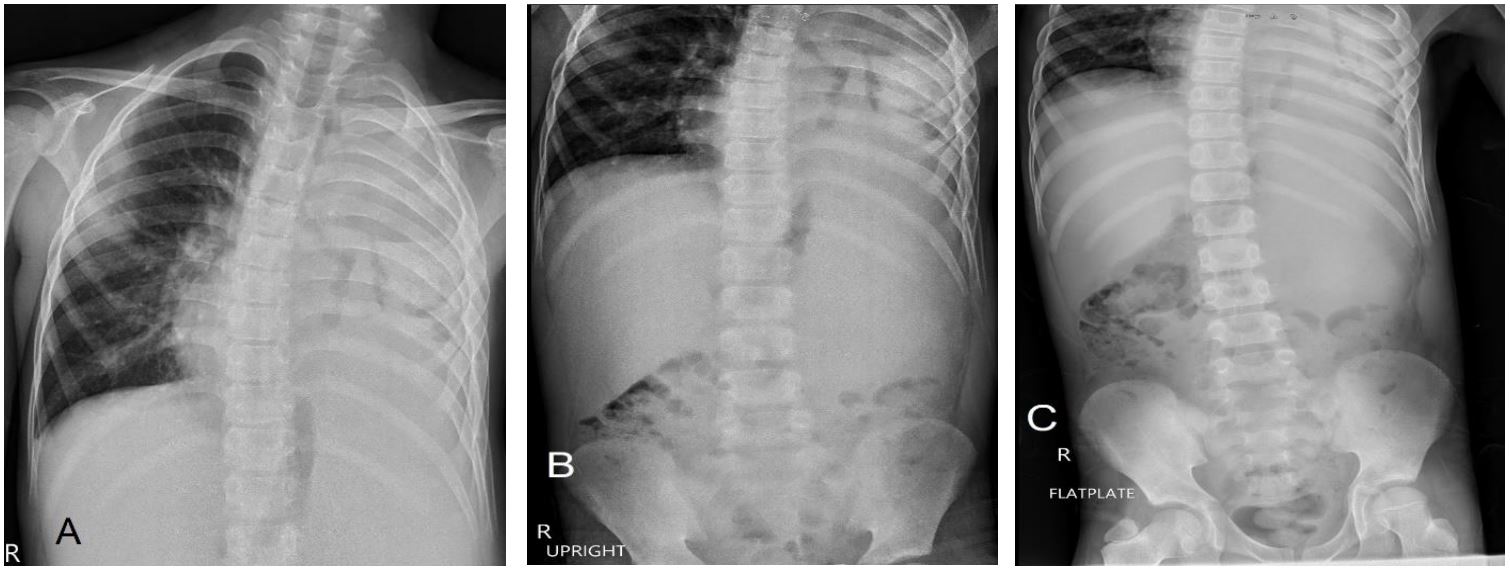

Figure 1: Radiographs on admission. (A) Chest AP view showing near-total opacification of the left hemithorax with trace lucencies and (B-C) Abdominal images showing soft tissue fullness in the left hemiabdomen which appears to extend into the ipsilateral hemithorax with inferomedial displacement of the gas-filled bowel loops.

We present a case of P.M. An 11-year-old who initially presented with a three-week history of cough, Intermittent fever, and dyspnea. The initial diagnosis of left congenital diaphragmatic hernia was suspected from the chest radiograph and ultrasound in another institution as an opacified left hemithorax and bowel loops within the left thoracic cavity were found, respectively. The patient was subsequently referred to our institution where chest radiograph (Figure 1), chest ultrasound (Figure 2) and contrast-enhanced CT scan of the chest and upper abdomen (Figure 3-7) were done showing left perinephric and left psoas abscesses with intra-thoracic extension, probably through a left diaphragmatic defect, forming empyema thoracis and empyema necessitans. Culture of abscess fluid yielded no bacterial growth but GenExpert test was positive for M. tuberculosis.